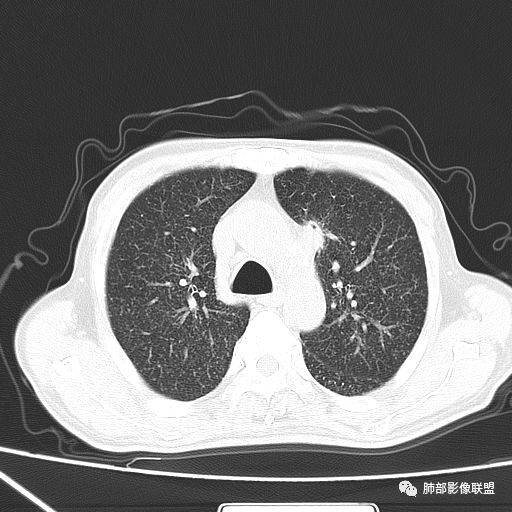

2019年9月12日CT(外院片,手机拍摄)

2019-10-20复查CT如下:

两肺弥漫性粟粒样结节伴左上肺小结节,呈三均匀分布,有结核的临床表现,支持血性播散性肺结核。

大小、分布均匀,边缘清楚

细小结节,弥漫,撒米粒样——血道来源

部分可见分支状

边缘稍平直

毛刺细弱

还是支持结核

血道来源的病灶,均匀、细微,而且部分有分支状,都符合粟粒型肺结核

10月20日的CT其实是抗痨治疗近1月复查的CT。患者来我院后抗痨治疗体温下降,症状明显好转。

急性血行播散型肺结核  两肺广泛分布粟粒大小的结节状密度增高影,具有大小均匀、分布均匀、密度均匀的典型“三均匀”特征,注意急性血播病灶非常小,一般粟粒影直径1~2mm。

病灶密集者出现肺外围血管影不清或减少。

发热初期肺部可缺乏典型影像学改变,1到2周后出现的广泛粟粒结节对诊断具有高度提示作用!